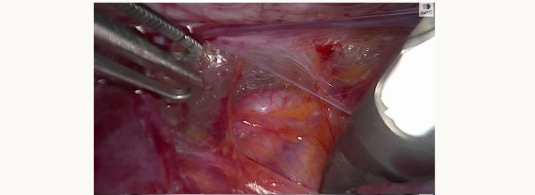

Figure 2A

Figure 2B

Helping to see the ureter more laterally in the pelvic sidewall can allow safe occlusion of the uterine artery at its source (figures 2A and 2B above) which can be helpful during myomectomies or more complex hysterectomies.